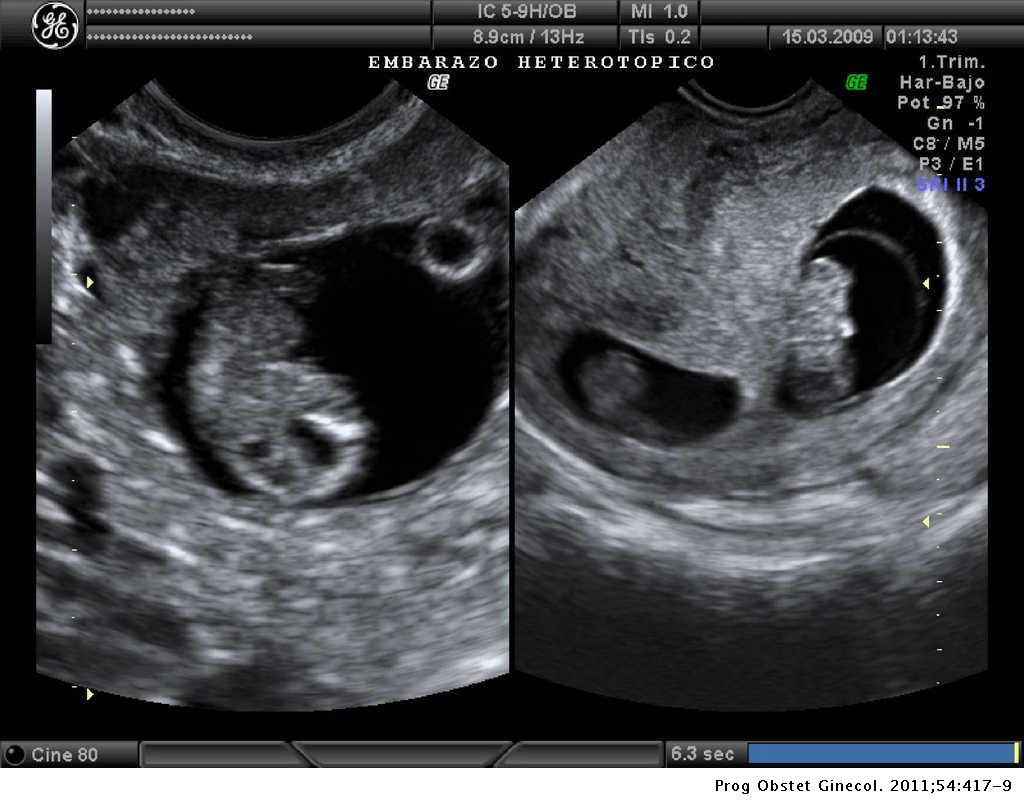

Artículos Gestación heterotópica triple: gestación gemelar intrauterina viral